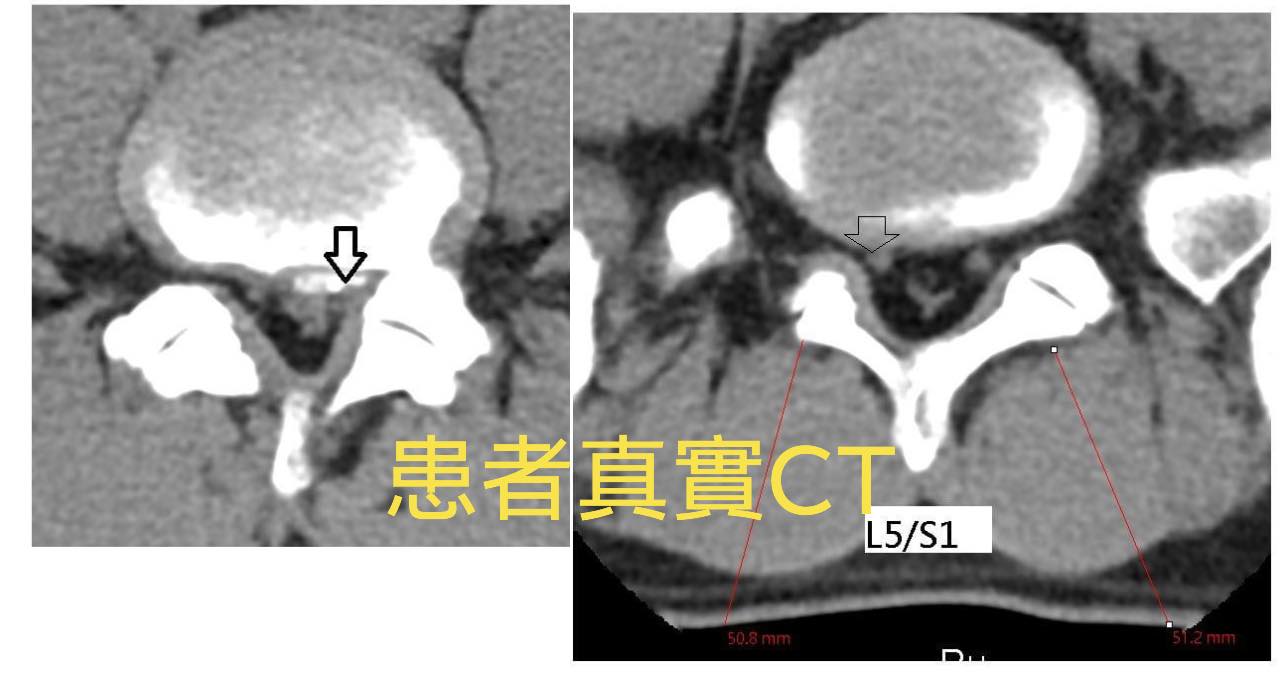

⭐️首先先說下椎間盤的結構,椎間盤位於兩個椎體之間用於承重和鏈接,主要有裡面的髓核和外面纖維環組成。這就是一個正常的腰椎間盤CT,可以看到椎間盤沒有變扁向周圍膨出或突出

⭐️ 當受到外力壓迫的時候,椎間盤就會變扁,這時髓核還在纖維環裡面,就好比一個豆沙包被壓扁了,豆沙餡還在包子里,椎間盤變扁就會向周圍膨出,壓迫後面的硬膜囊和後緣兩側的神經根,就會造成腰腿疼痛,感覺異常、麻木等,下面這個就是一個膨出的患者的CT表現。膨出一般可以休息、理療自行緩解。

1.L4L5;L5S1輕微椎椎間盤突出->中間偏左

❇️術前溝通:片子上看起來突出不嚴重也沒脫垂,患者也沒有大小便失禁的症狀,也沒有大小便疼痛,也沒有垂足跟腳萎縮情況,估計脊髓沒損傷,只是突出的椎間盤壓迫神經根導致,安排三週治療看效果如何,如果有改善就繼續治療,如果還是麻痛到不行就建議開刀